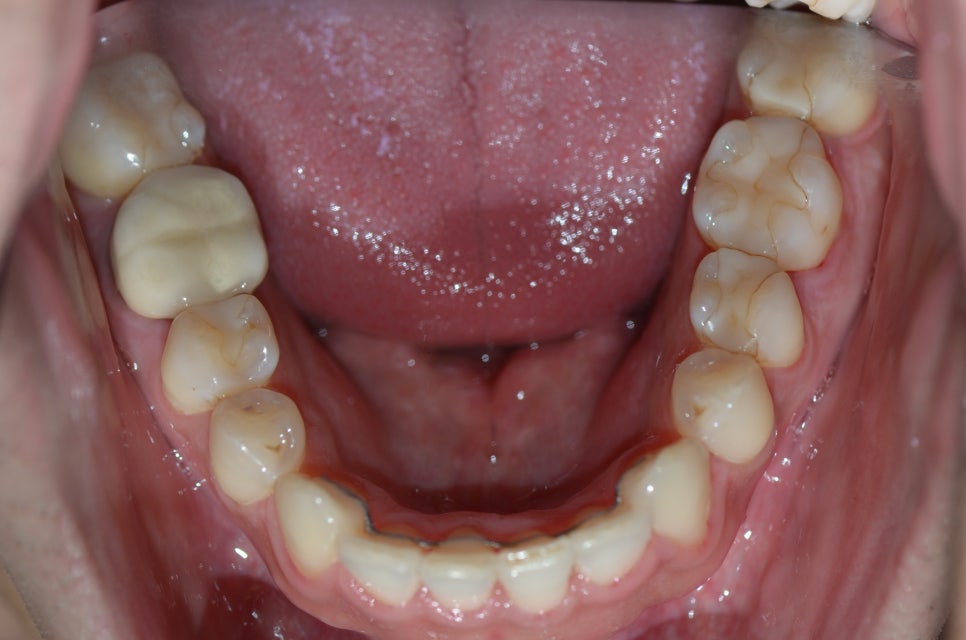

이분은 아래 앞니가 하나 완전히 겹쳐서 나있으신데요

이 경우에는 여러가지 방법을 이용해서 비발치교정이 가능합니다

예쁘게 교정하고 마무리 유지장치까지 붙였습니다.